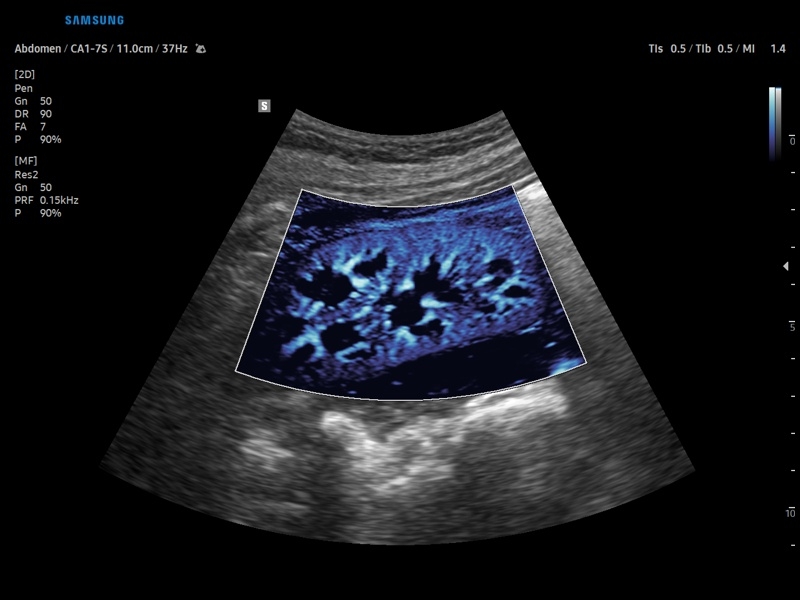

• Контрастное усиление CEUS+

• Модуль CEUS+ (Contrast Enchansment UltraSound) - программа, позволяющая проводить обследование с применением контрастных агентов.

• Модуль MV-Flow – программа (режим), позволяющая визуализировать кровоток в микроциркуляторном русле с высоким разрешением без использования контраста.

• Модуль MV-Flow - программа (режим), позволяющая визуализировать кровоток в микроциркуляторном русле с высоким разрешением без использования контраста.